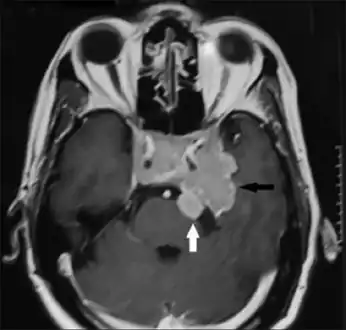

A doctor will test for prolactin blood levels in women with unexplained milk secretion (galactorrhea) or irregular menses or infertility, and in men with impaired sexual function and, in rare cases, milk secretion. If prolactin is high, a doctor will test thyroid function and ask first about other conditions and medications known to raise prolactin secretion. The doctor will also request a magnetic resonance imaging (MRI), which is the most sensitive test for detecting pituitary tumors and determining their size. MRI scans may be repeated periodically to assess tumor progression and the effects of therapy. CT scan also gives an image of the pituitary, but it is less sensitive than the MRI.

In addition to assessing the size of the pituitary tumor, doctors also look for damage to surrounding tissues, and perform tests to assess whether production of other pituitary hormones is normal. Depending on the size of the tumor, the doctor may request an eye exam with measurement of visual fields.

Invasive prolactinoma showing invasion into the left temporal lobe

Prolactinoma on MRI